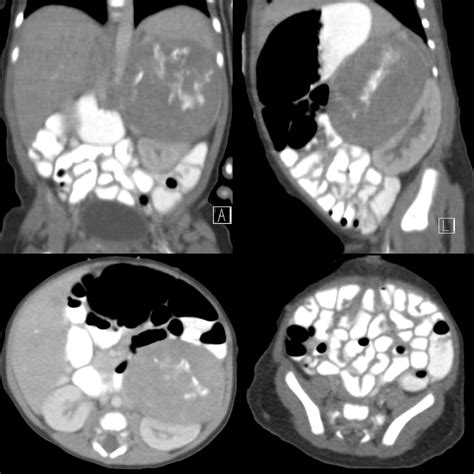

• Computed Tomography (CT): Provides detailed cross-sectional views, used when high-definition structural information is required.

CT Scan Moderate Complex trauma, internal injuries, detailed anatomy